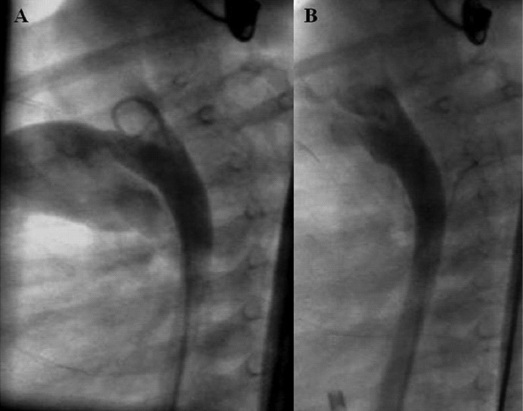

El síndrome de Rubinstein-Taybi es producido por una anomalía genética y se caracteriza por una facies típica, anomalías de manos y pies, microcefalia y retraso mental. Alrededor del 30% de los individuos afectados tienen defectos cardíacos congénitos asociados. En esta presentación se describen los casos de dos pacientes con diagnóstico de síndrome de Rubinstein-Taybi asociado con alteraciones cardíacas congénitas. Uno de ellos, de 25 años, presentaba coartación de la aorta nativa, localizada en la región yuxtaductal, y el otro, de 11 meses de edad, mostraba un conducto arterioso permeable de tamaño grande. Ambos pacientes recibieron tratamiento intervencionista percutáneo exitoso, con evolución alejada satisfactoria.